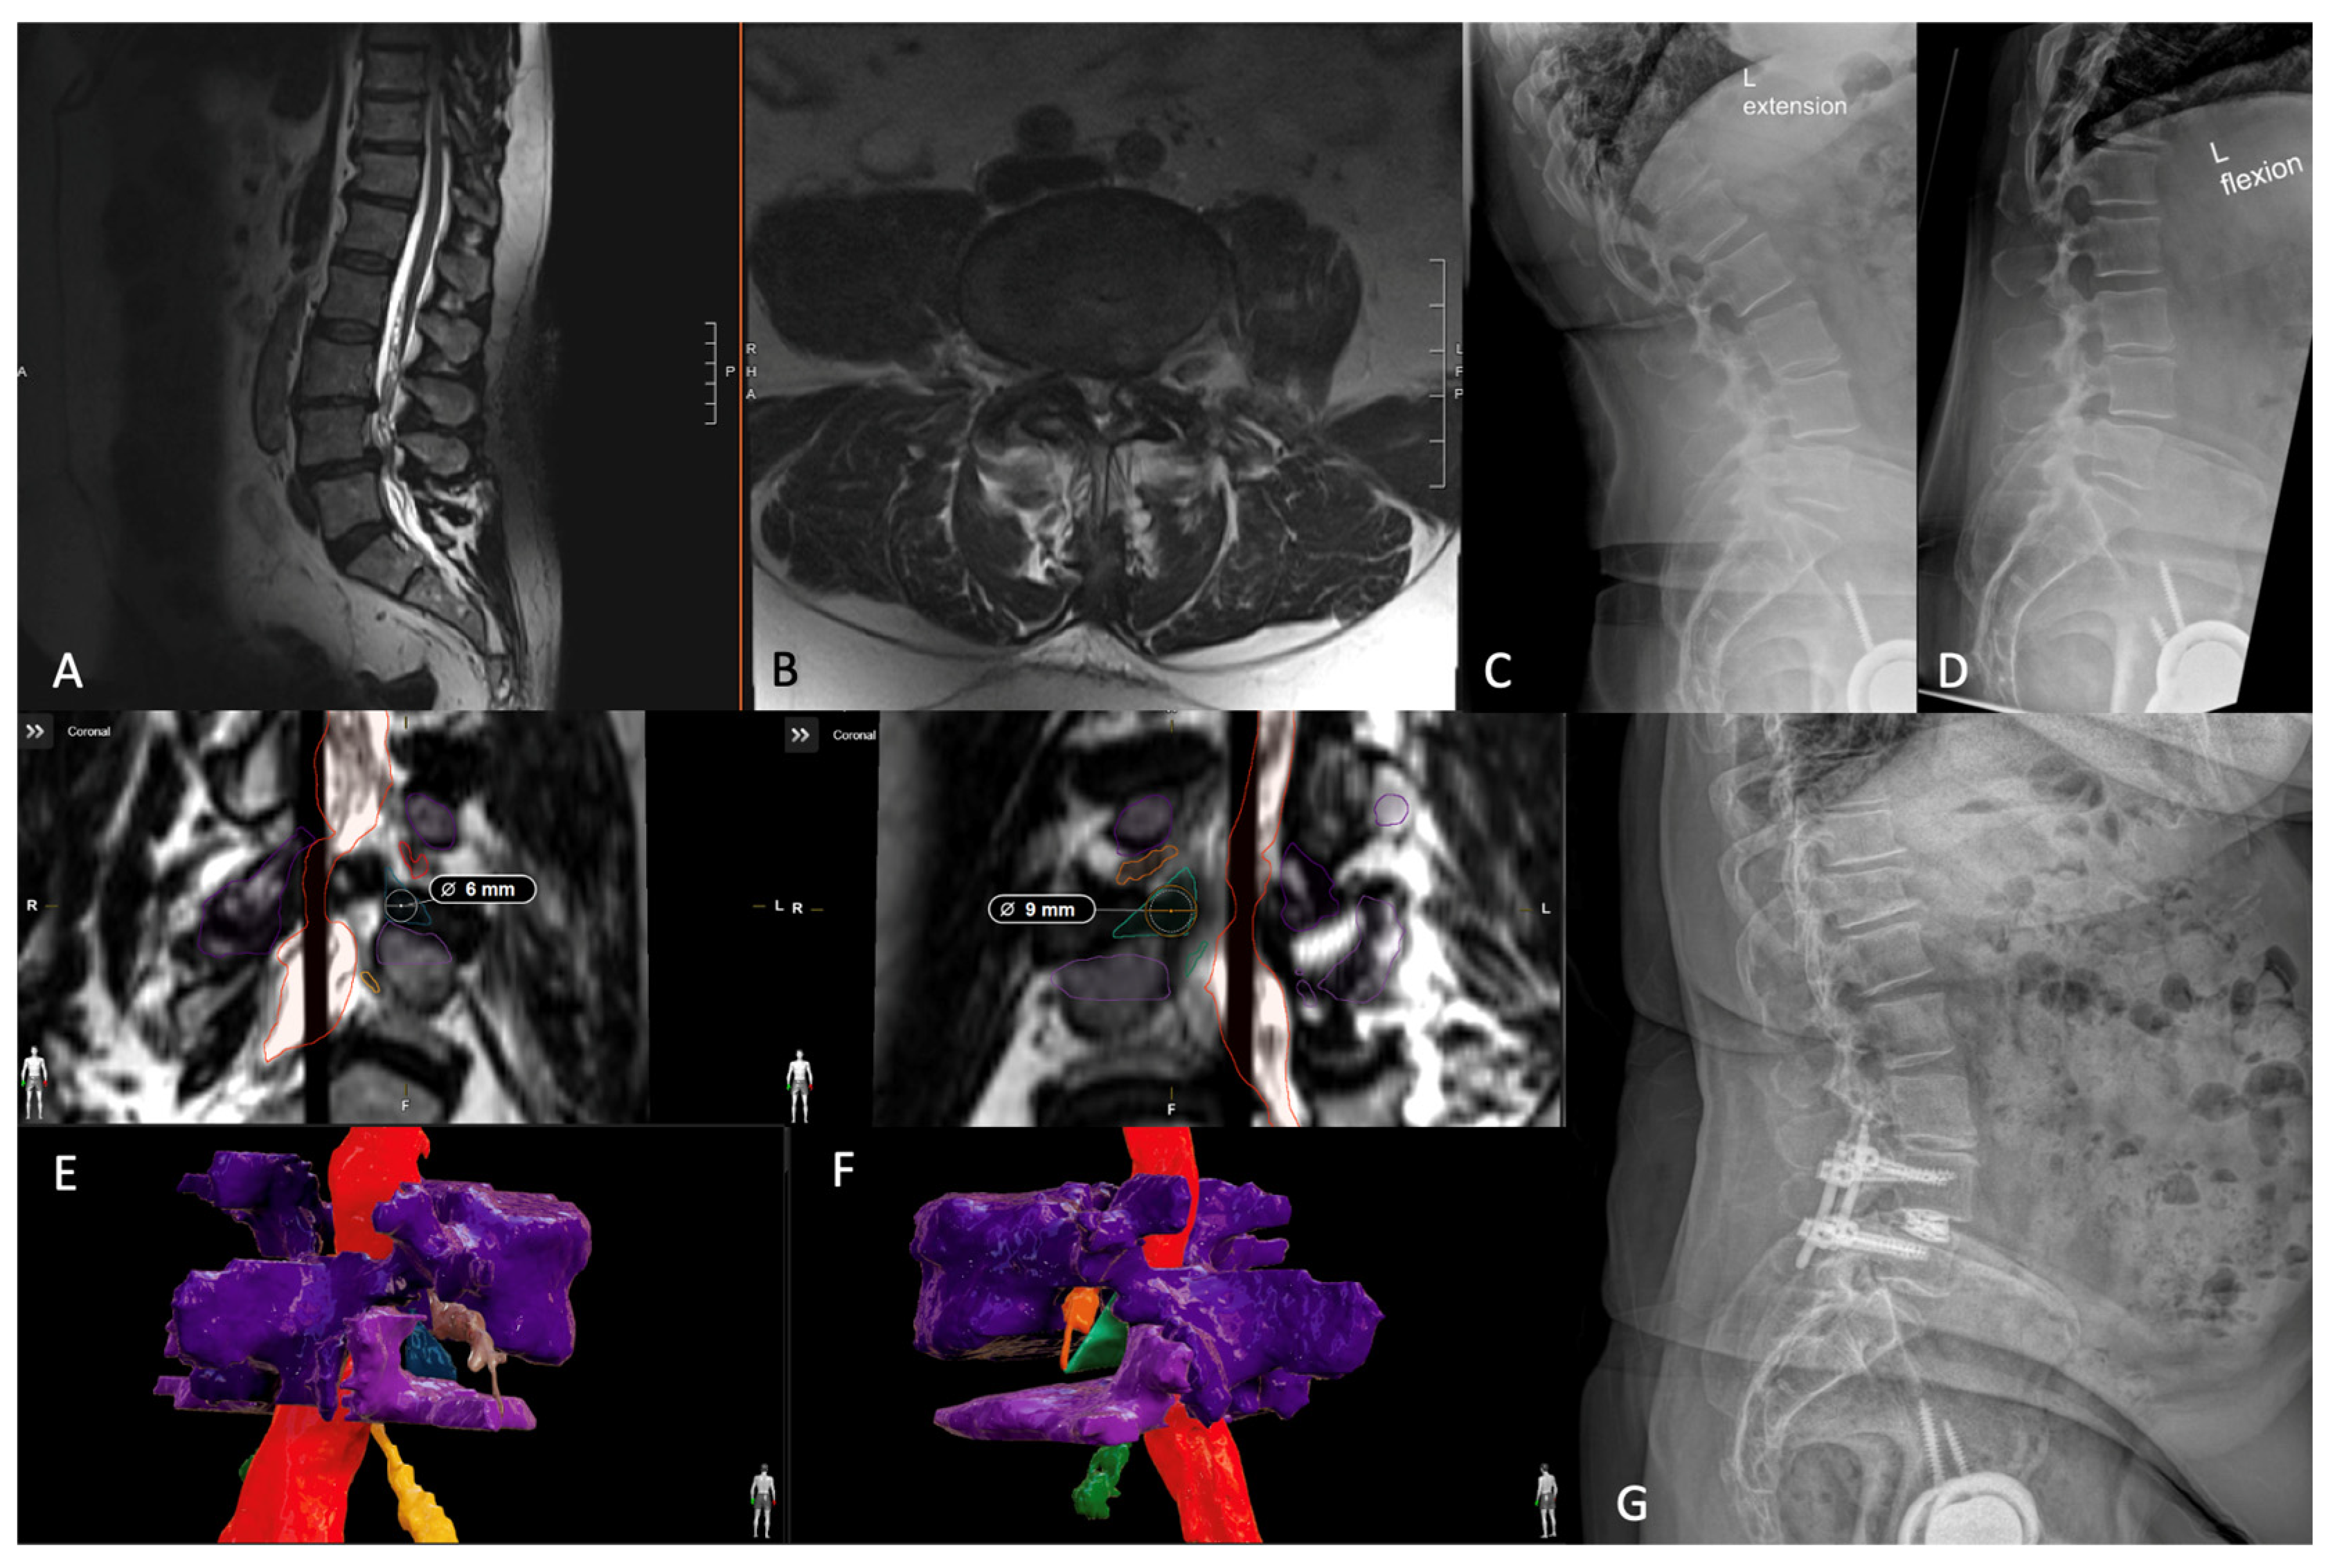

7.2. Three-Dimensional Neurosegmentation

- Tabarestani, T.Q.; Salven, D.S.; Sykes, D.A.W.; Bardeesi, A.M.; Bartlett, A.M.; Wang, T.Y.; Paturu, M.R.; Dibble, C.F.; Shaffrey, C.I.; Ray, W.Z.; et al. Using Novel Segmentation Technology to Define Safe Corridors for Minimally Invasive Posterior Lumbar Interbody Fusion. Oper. Neurosurg. 2023. [Google Scholar] [CrossRef] [PubMed]

- Tabarestani, T.Q.; Sykes, D.A.W.; Kouam, R.W.; Salven, D.S.; Wang, T.Y.; Mehta, V.A.; Shaffrey, C.I.; Wiggins, W.F.; Chi, J.H.; Abd-El-Barr, M.M. Novel Approach to Percutaneous Lumbar Surgeries via Kambin’s Triangle-Radiographic and Surgical Planning Analysis with Nerve Segmentation Technology. World Neurosurg. 2023, 177, e385–e396. [Google Scholar] [CrossRef] [PubMed]

- Tabarestani, T.Q.; Sykes, D.A.W.; Maquoit, G.; Wang, T.Y.; Ayoub, C.M.; Shaffrey, C.I.; Wiggins, W.F.; Abd-El-Barr, M.M. Novel Merging of CT and MRI to Allow for Safe Navigation into Kambin’s Triangle for Percutaneous Lumbar Interbody Fusion-Initial Case Series Investigating Safety and Efficacy. Oper. Neurosurg. 2023, 24, 331–340. [Google Scholar] [CrossRef] [PubMed]